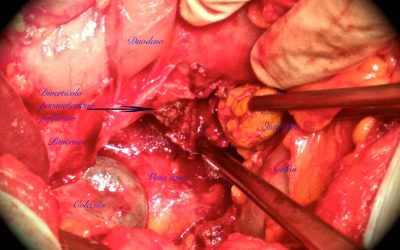

Perforazione di diverticolo duodenale paravateriano da duodenolita: segnalazione di un caso e osservazioni sul trattamento della perforazione diverticolare paravateriana

di Enrico Ganz I diverticoli duodenali sono riscontrati nel 4%-18% della popolazione (14,37,39,45); il loro diametro varia normalmente tra 1 cm e 5 cm (40). Nella maggior parte dei casi essi non producono sintomi per l’intero corso della vita; diventano...